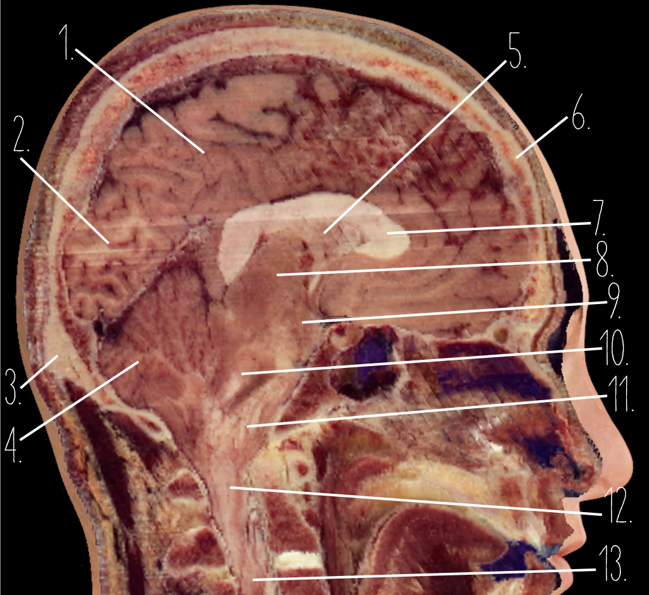

Brain Cross Sectional

1

Frontal Bone

2

Frontal Lobe

3?

Falx Cerebri

4?

Gray Matter

5?

White Matter

6?

Sulcus

7?

Gyrus

8?

Fissure

1?

Parietal Lobe

2?

Cerebellum

3?

Occipital Bone

4?

Cerebellum

5?

Lateral Ventricle

6?

Frontal Bone

7?

Corpus Callosum

8?

Thalamus

9?

Hypothalamus

10?

Midbrain

11?

Pons

12?

Medulla Oblongata

13?

Spinal Cord